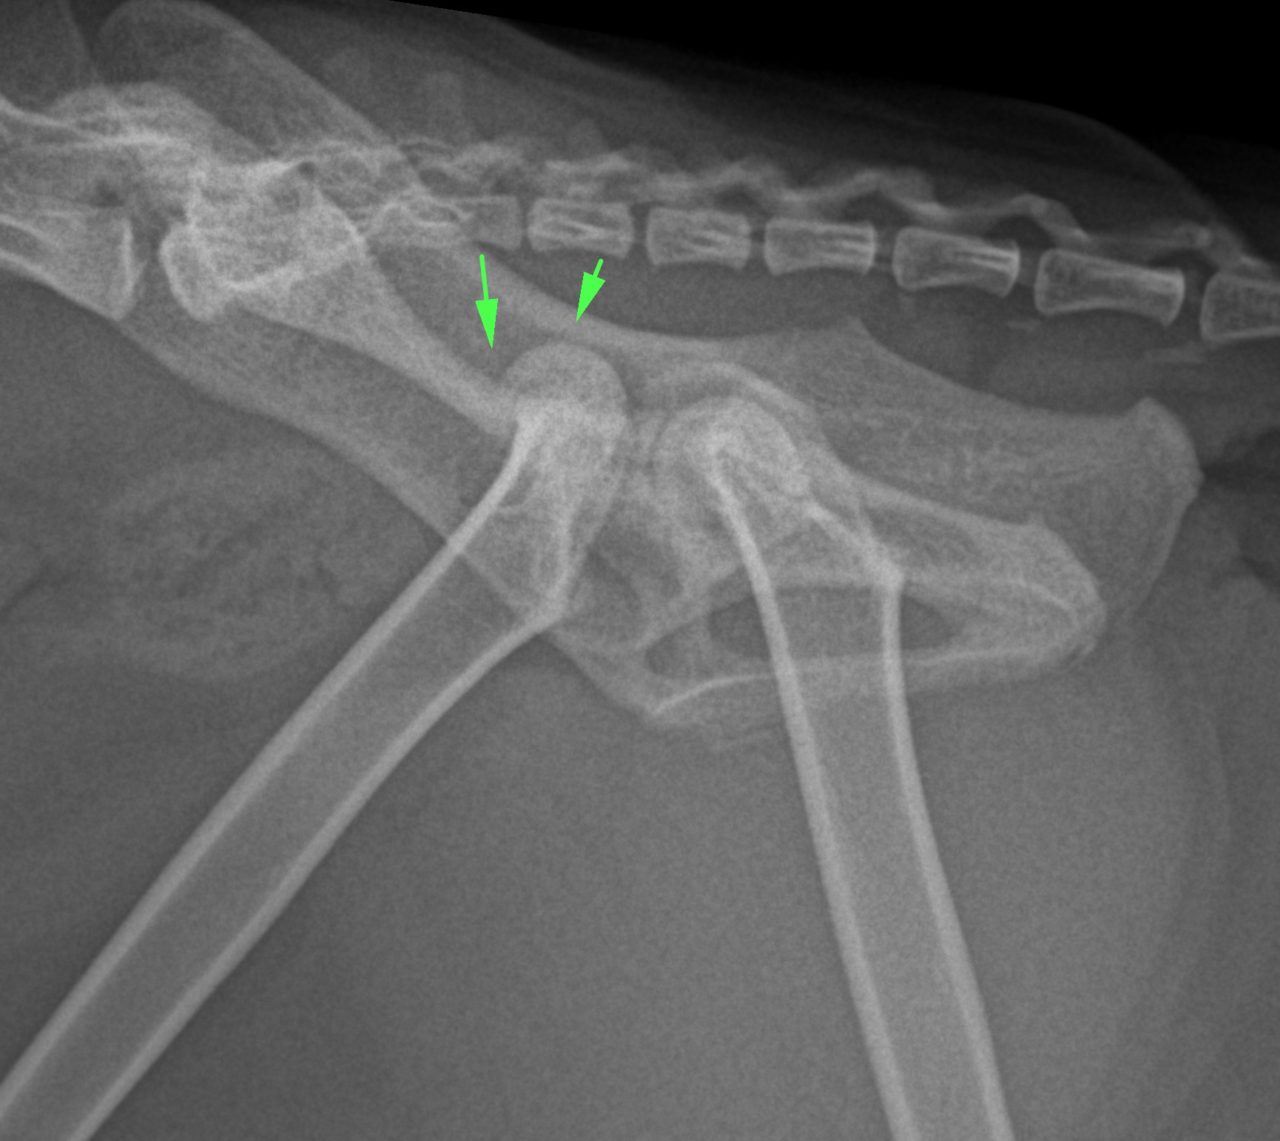

猫の股関節脱臼 外出から帰宅すると猫ちゃんが右後肢を跛行しているとのことで、救急で来院されました。エックス線では右股関節の背側前方脱臼が確認されました。トグルピンと人工靱帯により脱臼した大腿骨を寛骨内に整復します。しばらく安静が必要となります。 症例カテゴリー 放射線治療整形外科軟部組織外科脳神経外科内科腫瘍外科救急・集中治療リハビリテーション科腫瘍内科内視鏡科脳神経科呼吸器外科中医・漢方猫の腎移植循環器科